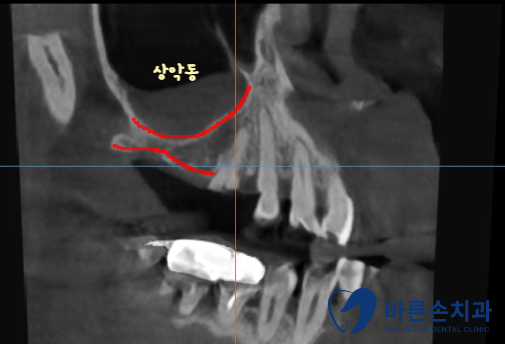

임플란트를 심기 위해서는 뼈가 충분히 있어야 하는데

상악동(빈 공간) 아래로 뼈가 너무 얇습니다.

상악동을 들어올려서 뼈이식을 충분히 하고 임플란트를 식립하기로 합니다.

이 수술 방법을 상악동 거상술이라고 해요.

좌우 모두 뼈를 만들면서 임플란트를 식립합니다.